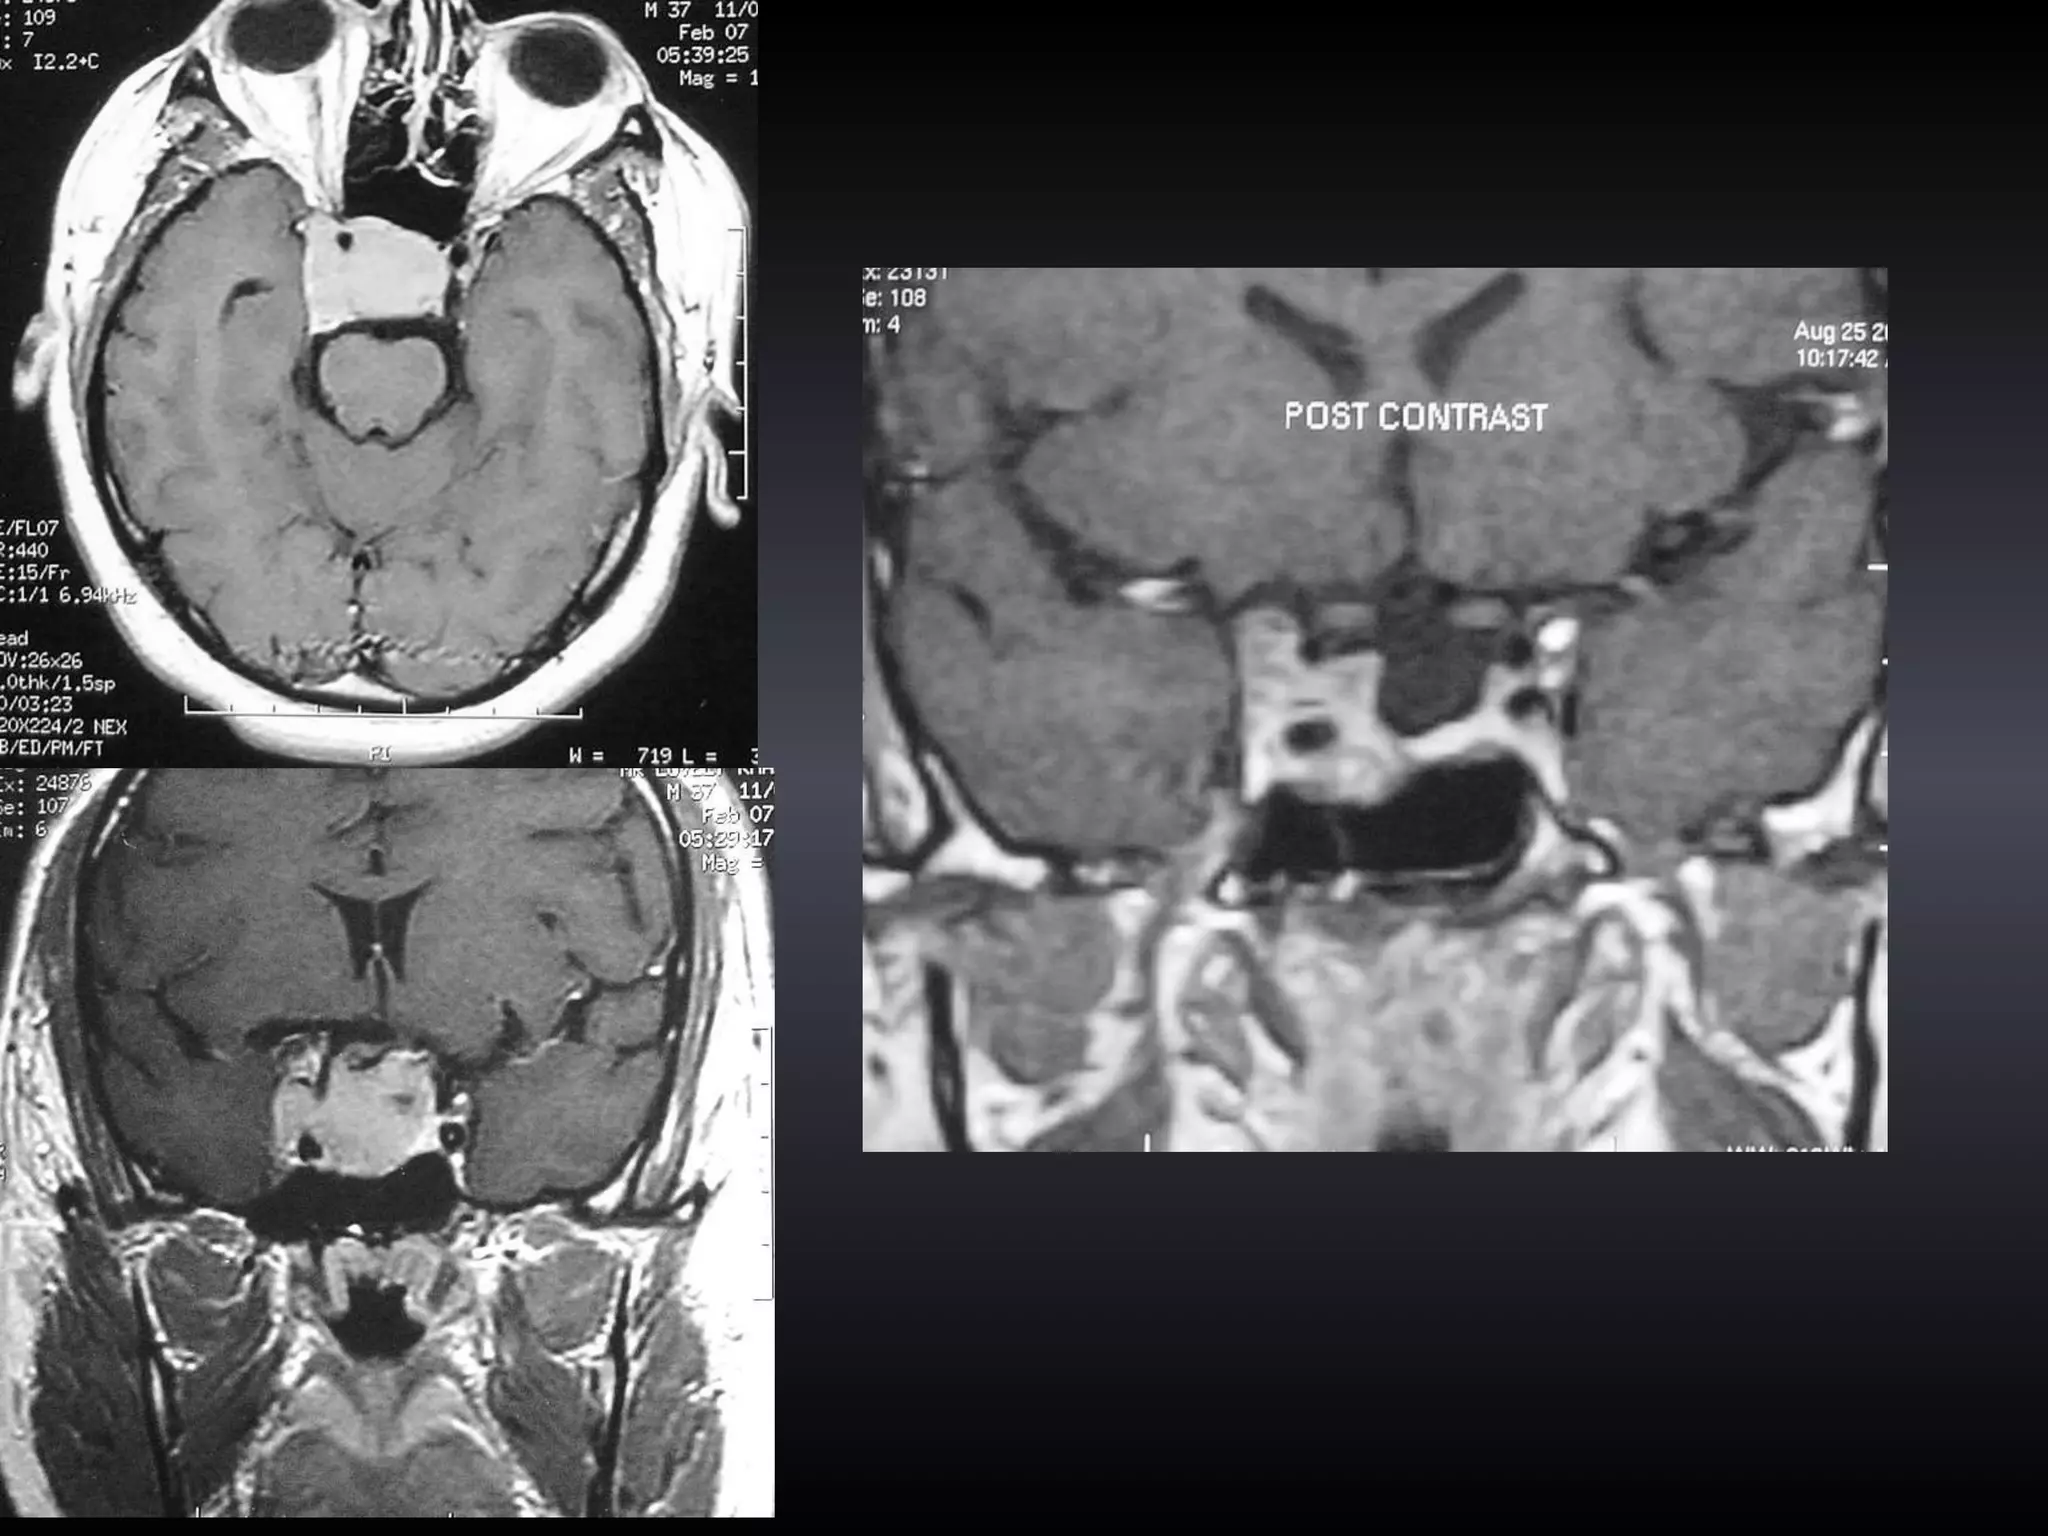

VITAMIN E CAPSULES

FLAIR T2 FATSAT

TECHNIQUE Image Guidance in Trans-sphenoidal surgery

TECHNIQUE

OBSERVATIONS Seven pts underwent IG pit ad surgery Three patients had giant Pit ad Two had recurrent/residual disease Image Guidance in Trans-sphenoidal surgery

OBSERVATIONS 3 patients (all giant tumors) non-contrast MR images were used in for image guidance and contrast CT images were used in the rest  Image Guidance in Trans-sphenoidal surgery